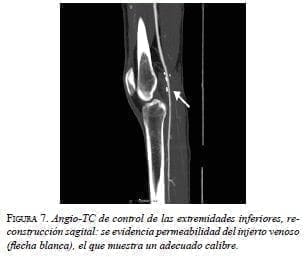

Con la confirmación diagnóstica de enfermedad quística de la adventicia, se decidió intervenirlo quirúrgicamente. Se utilizó un abordaje posterior de la fosa poplítea (figura 4) que expuso la lesión quística dependiente de la pared arterial. Se resecó el segmento afectado (figura 5) y se reparó el defecto con intercalación de injerto autólogo de vena safena (figura 6). El paciente evolucionó favorablemente, sin complicaciones inmediatas. Acudió a control meses después de la cirugía, sin síntomas. Se practicó una angiografía por tomografía computadorizada (TC) de control, que demostró un adecuado flujo sanguíneo en el injerto (figura 7).